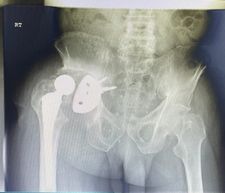

71-year old male with a right total hip following fracture dislocation 21 years ago presents with a 6 month history of increasing pain and shortening of the right lower limb. Recommended for acetabulum revision. Performed with graft multi hole revision cup and change of femoral head to 36 mm